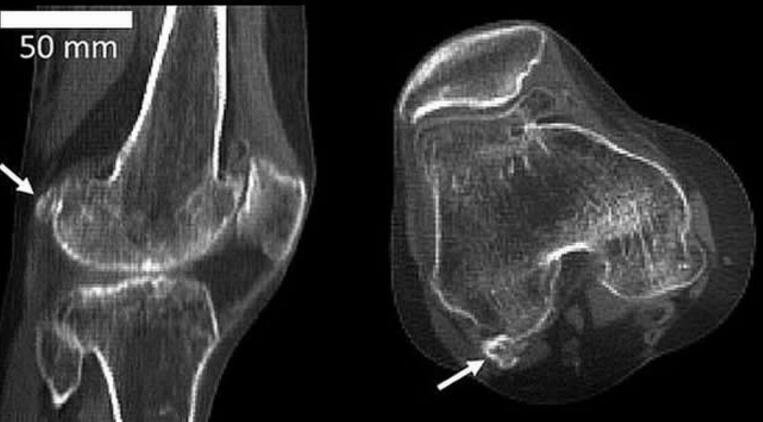

图中显示3个不同膝骨样本存在不同大小的豆骨。科学家发现1918年全球11.2%居民体内存在豆骨,但截至2018年,全球39%居民体内存在豆骨。

英国伦敦帝国理工学院的研究人员回顾了过去150多年进行的2.1万多项科学研究,其中包括研究人员扫描和解剖鉴定发现豆骨的存在。他们从中发现1918年全球11.2%居民体内存在豆骨,但依据发表在《解剖学杂志》的这篇评论报告,截至2018年,全球39%居民体内存在豆骨。

伯托姆博士称,当远古灵长目动物进化成大猿和人类,我们似乎已不再需要豆骨,现在它只会给我们带来麻烦,但有趣的是,近年来人体出现豆骨的概率骤增。这项最新研究发表在《解剖学杂志》上,作者详细研究了25个国家21676个膝盖数据,最早的数据可追溯至1875年。这些膝盖数据来自多种渠道,其中包括:X射线、核磁共振扫描和局部解剖。